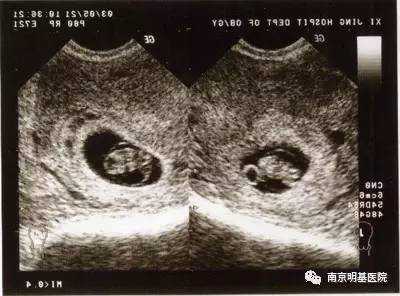

3.孕7周:心脏搏动明显,可显示胎体头极和尾极,并见小肢芽,这时候三维超声会看见宝宝像一个小蚕豆一样。

4.孕8周:初具人形,各部分迅速发展,头颅、躯干、四肢显示越来越清楚。